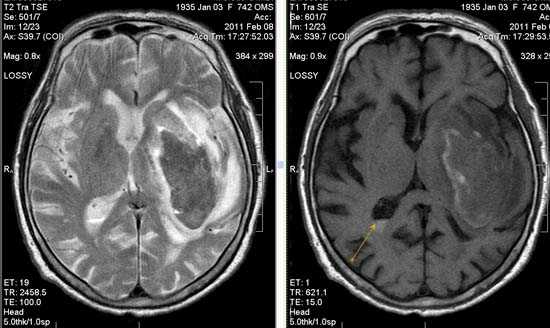

Зона подострого ишемического НМК, в бассейне правой средней мозговой артерии. В режиме Т1 визуализируется симтом «вуалирования»- изоинтенсивность МР-сигнала.

Подострая стадия ишемического НМК. При внутривенном контрастировании определяется накопления КВ в бороздах на уровне зоны ишемии (гиральный тип усиления).